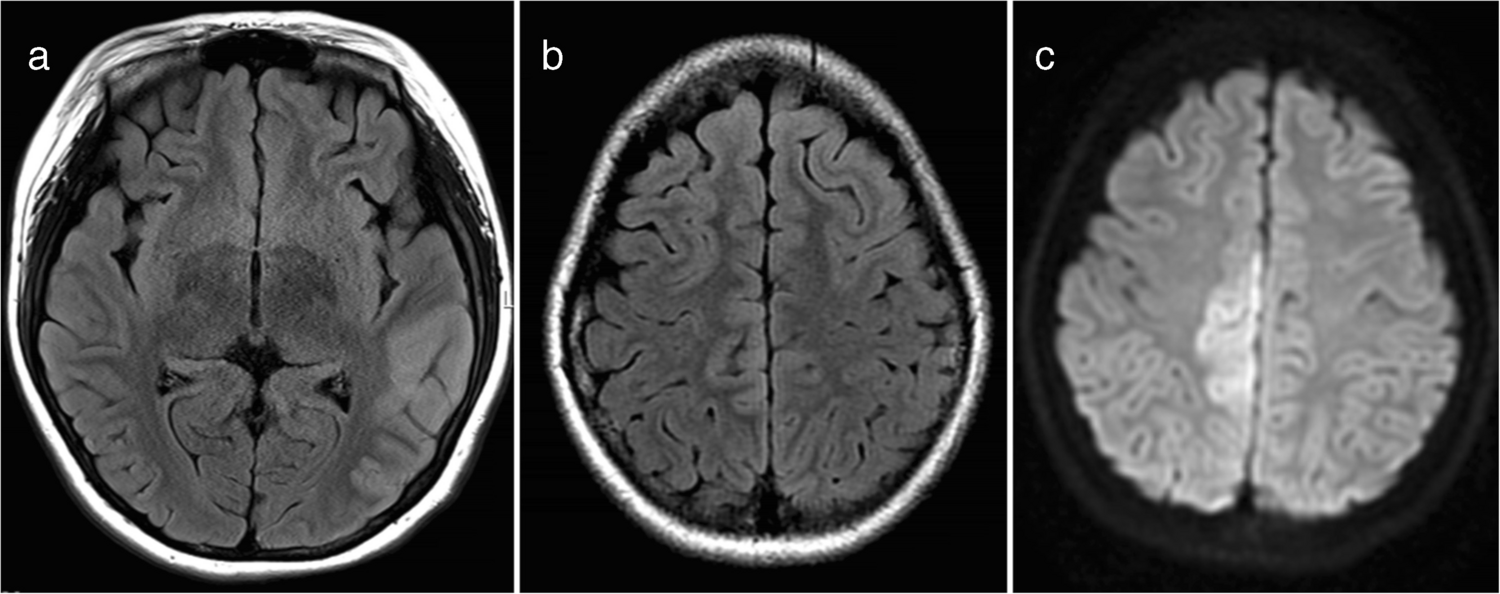

A cortical encephalitis pattern was identified in three patients, and an aseptic meningitis pattern was seen in six patients (Figs. 4 and 5, respectively). Tumefactive demyelinating lesions were observed in three cases. These lesions were large (> 2 cm) and unifocal, resembling either neoplastic processes or localized abscesses (Fig. 6). The lesions were located in the periventricular white matter, thalamus, and subcortical white matter/cortex, respectively. Unlike typical tumors, these lesions did not demonstrate mass effect. A cerebellitis/brainstem encephalitis pattern was found in two patients (Fig. 7). One patient exhibited non-enhancing lesions in the cerebellar white matter and midbrain, while the other had poorly defined cerebellar cortical lesions with curvilinear enhancement. Among the miscellaneous patterns, one patient showed a leukodystrophy-like presentation (Fig. 8a), and another exhibited an MS-like pattern (Fig. 8b–d).

Fig. 8

Magnetic resonance images illustrate myelin oligodendrocyte glycoprotein antibody-associated diseases of minor imaging patterns: a leukodystrophy-like pattern and a multiple sclerosis-like pattern. a Leukodystrophy-like pattern. Axial fluid-attenuated inversion recovery image from a 3-year-old girl with slurred speech, drooling, and right-sided weakness shows extensive, confluent, nearly symmetric white matter lesions resembling leukodystrophy. b, c, d Multiple sclerosis-like pattern. Three consecutive sagittal fluid-attenuated inversion recovery images from a 14-year-old boy demonstrate well-defined white matter lesions oriented perpendicular to the ventricles

A leukodystrophy-like pattern, considered a rare presentation, was identified in one case in our study. This phenotype has been recently reported in pediatric MOGAD and appears to occur more frequently in younger children [21]. In line with this, our case involved a 3-year-old girl. Another distinct pattern observed in our study was a multiple sclerosis-like presentation, seen in just one patient. This was characterized by small, well-defined white matter lesions oriented perpendicular to the ventricles. MOG antibodies are rarely linked to multiple sclerosis in the pediatric population [4], which may explain why only one such case was identified in our cohort. In the study by Baumann M et al., multiple sclerosis-like patterns were absent in the MOG-positive ADEM group, while two cases (14%) were observed in the MOG-negative ADEM group [24]. The patient with the multiple sclerosis-like pattern in our study was lost to follow-up, so we could not determine whether this represented true multiple sclerosis. It is also noteworthy that no cases of limbic encephalitis were detected in our cohort. Although MOGAD can present as limbic encephalitis [31], bilateral medial temporal lobe involvement is considered atypical for MOGAD [25]. Furthermore, limbic encephalitis generally presents at an older age compared to other MOGAD subtypes such as ADEM and cortical encephalitis [31].